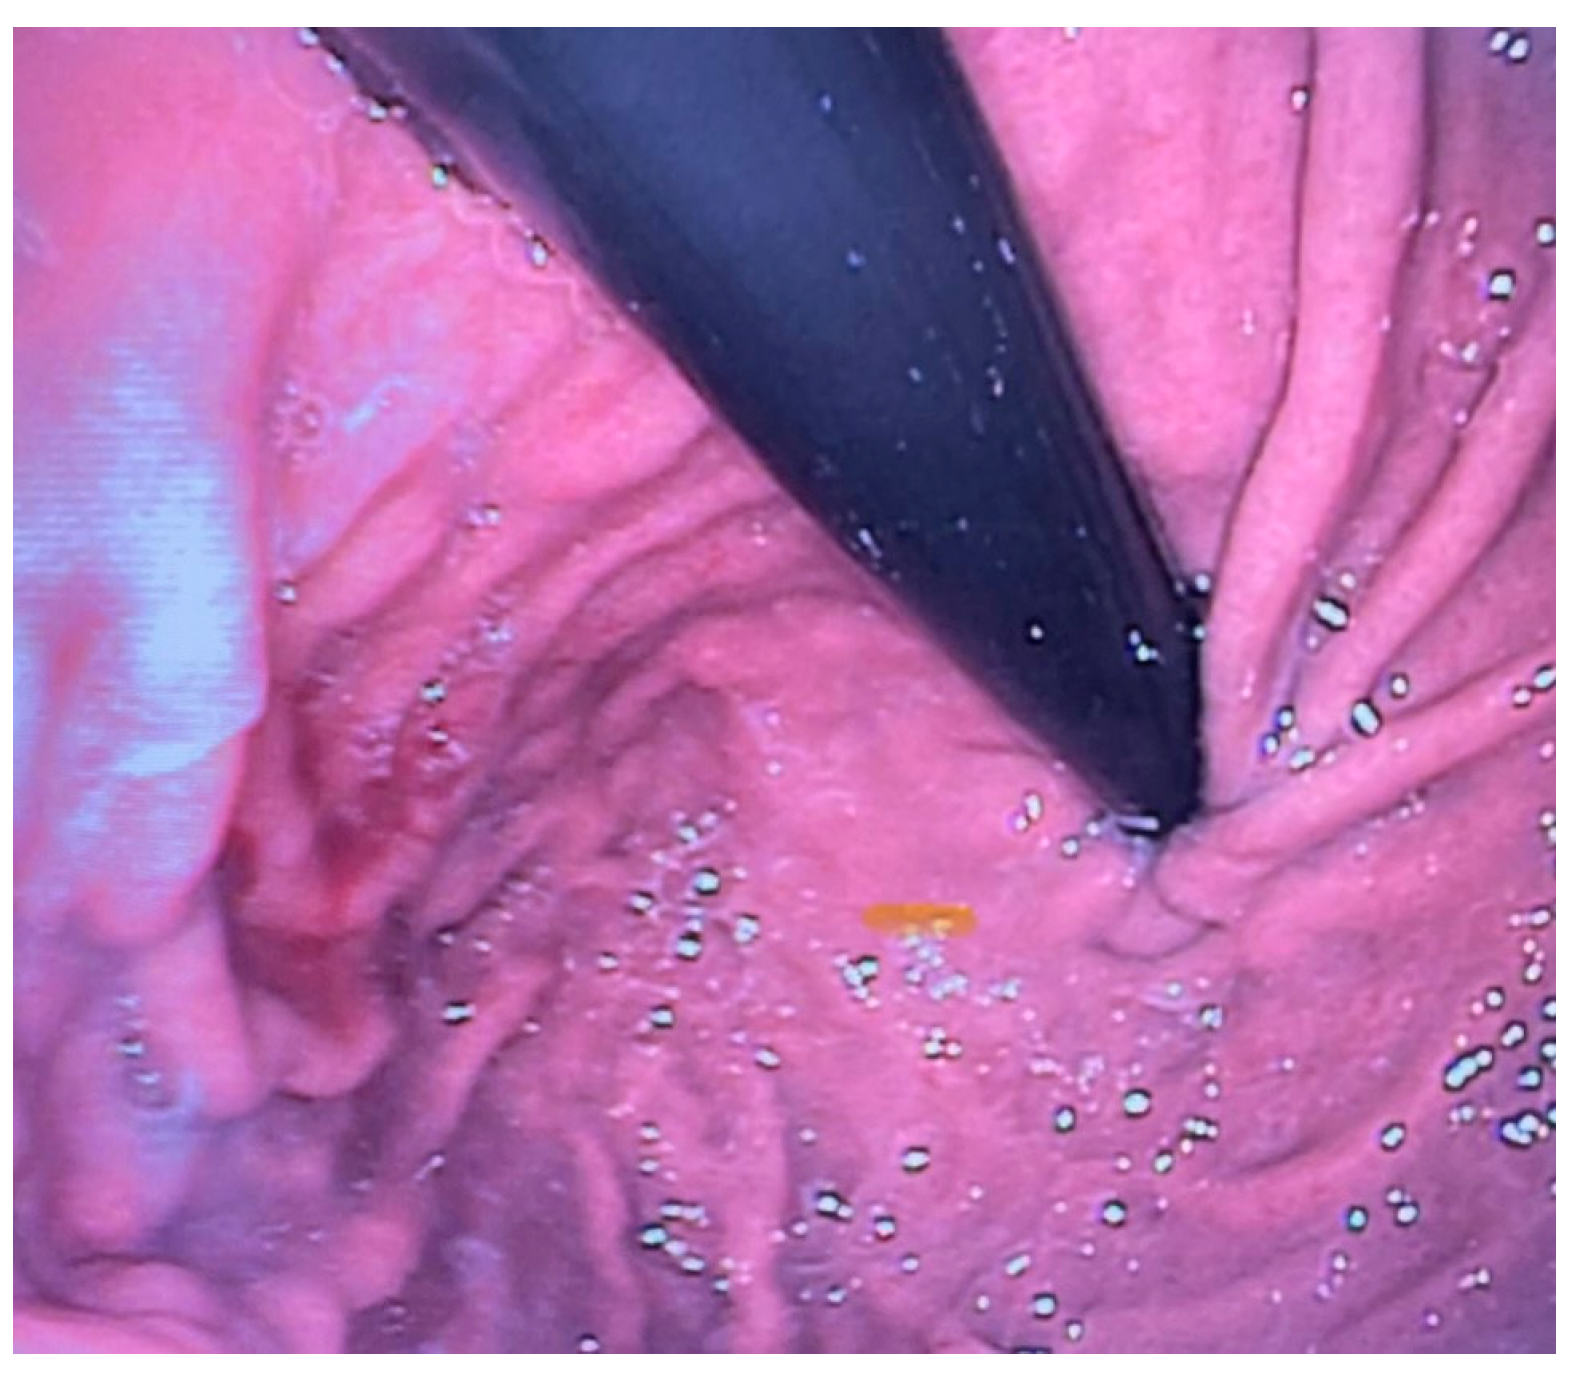

Esophagogastroscopy allowed us to obtain multiple pieces of information in our patients: it allowed us to assess both esophageal and gastric anatomy under direct vision, as well as the contractility of the lower esophageal sphincter. It also provided insights into the macroscopic characteristics of the esophageal and gastric mucosa (Figure 2 and Figure 3). Moreover, by performing at least four esophageal biopsies during each procedure, we were able to confirm the presence of esophagitis and classify its type, which could be a potential consequence of gastroesophageal reflux disease (GERD), using histopathological analysis [9].

Figure 3. Normal LES contractility on endoscopic examination.